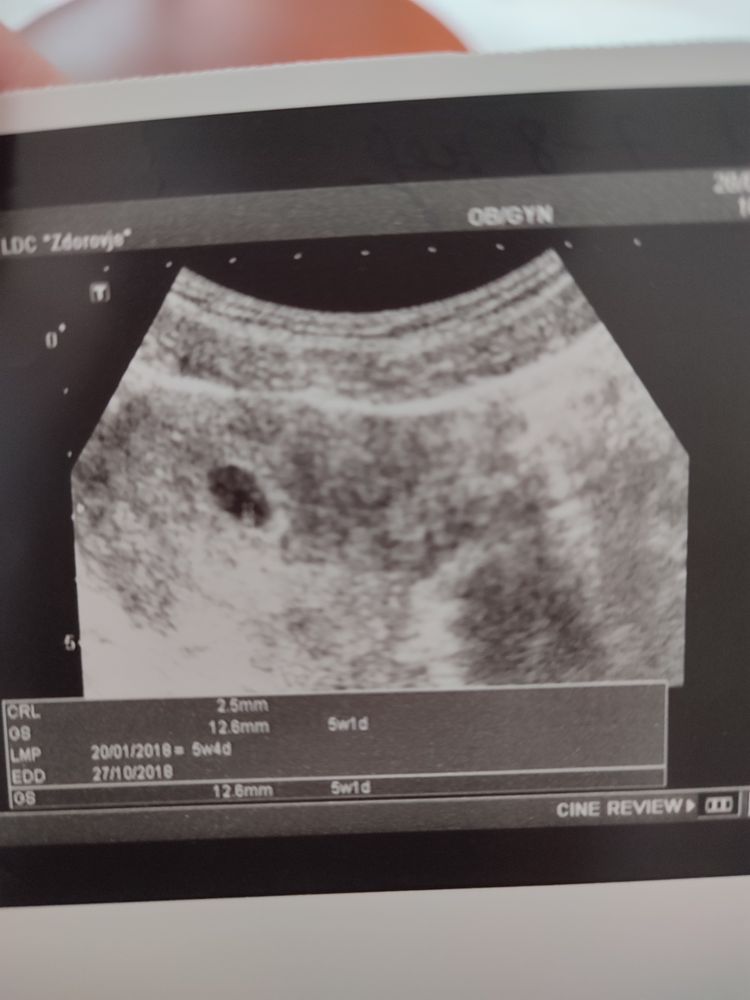

Вот сын, на сроке 6-7 недель